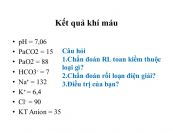

Khí máu là một xét nghiệm có giá trị, cung cấp nhiều thông tin cho các bác sỹ, đặc biệt là các bác sỹ làm việc tại các khoa Điều trị Tích cực về tình trạng toan kiềm. Mời các bàn eLib tìm hiểu thêm nhé!